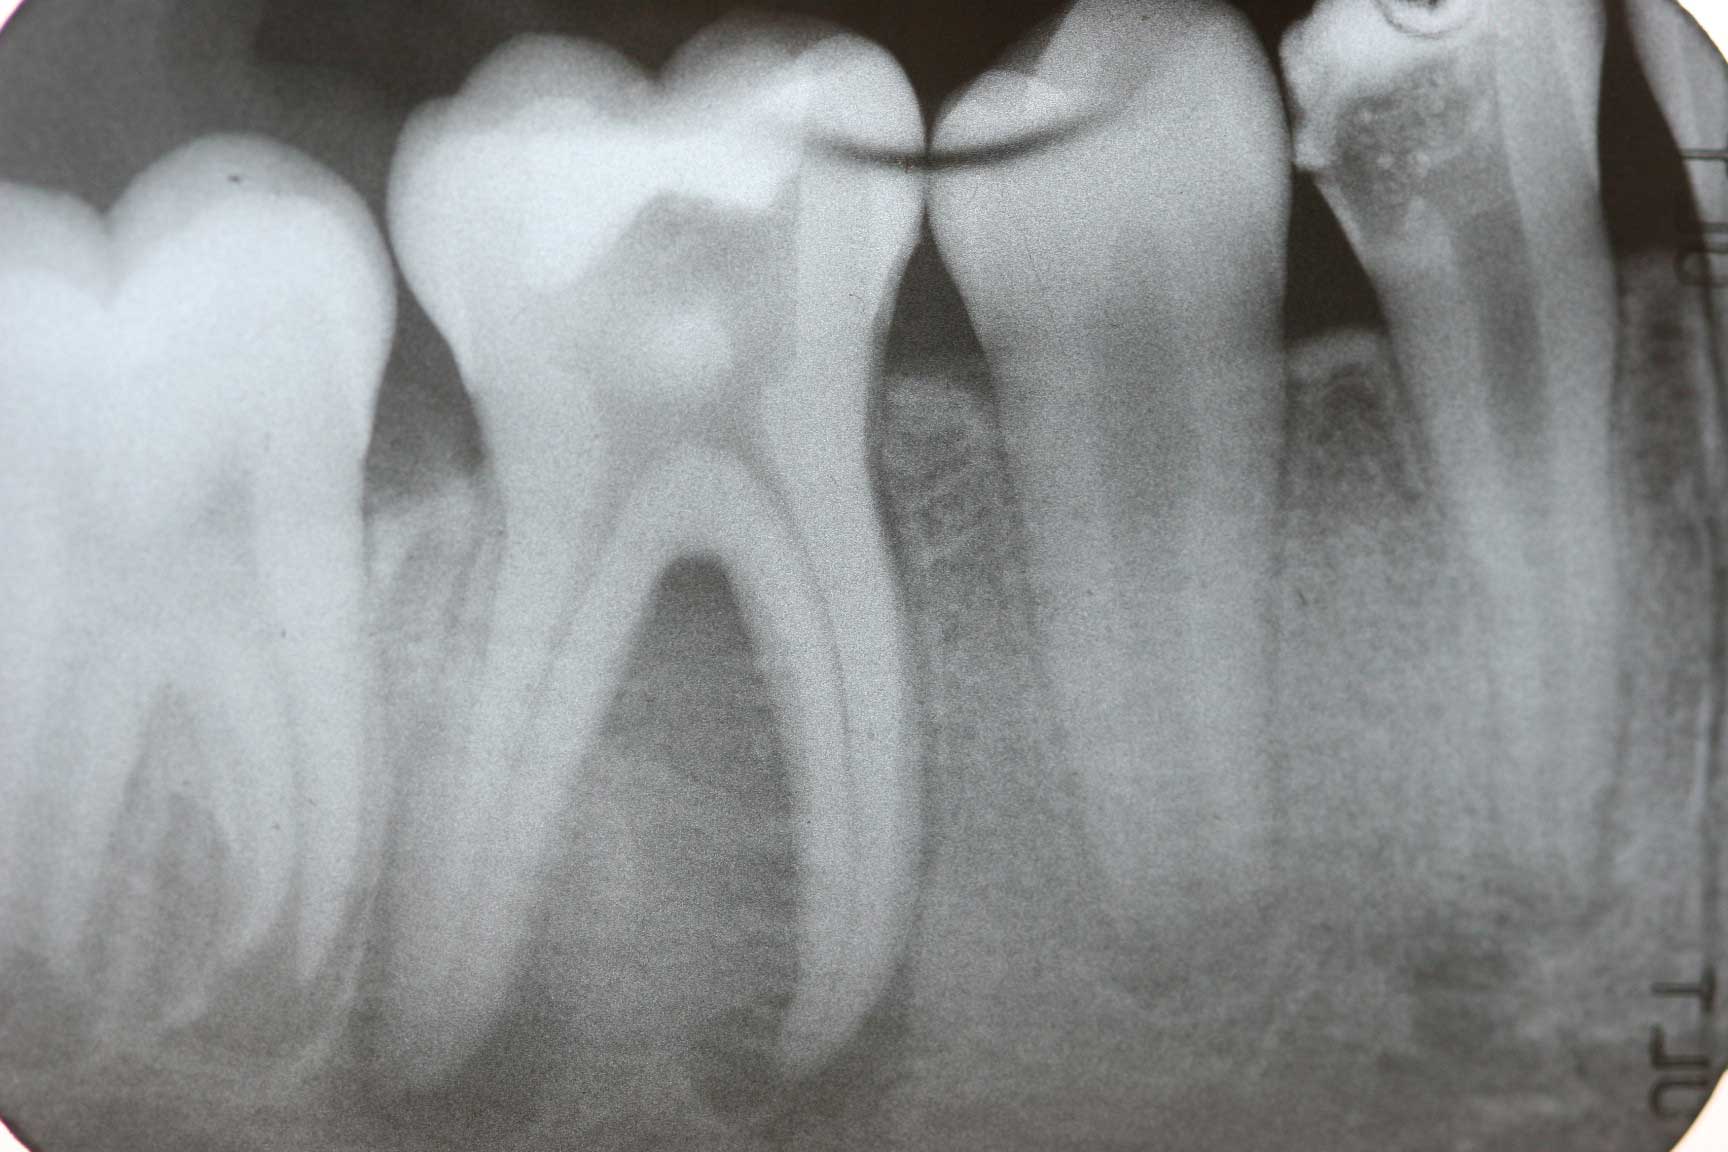

from galladental.com.my

Flow Dental Endodontic XRay Positioning Kit Galla Dental